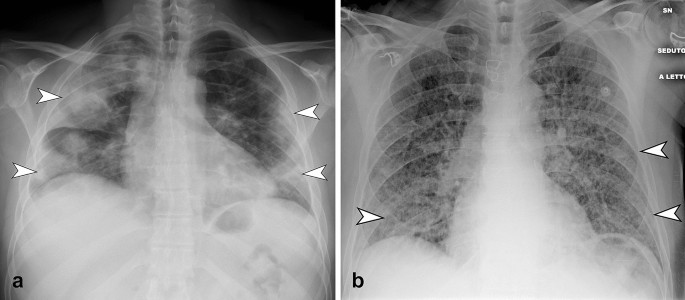

GGO is defined as an area of hazy increased lung opacity, less opaque than consolidation, within which margins of pulmonary vessels may be indistinct (Fig. 1a, b). Consolidation is defined as a homogeneous increase in pulmonary parenchymal attenuation that obscures the margins of vessels and airway walls (Fig. 2a). Reticular pattern is defined as a collection of innumerable small linear opacities that, by summation, produce an appearance resembling a net (Fig. 1c, d, Fig. 2b).

a CXR in postero-anterior view shows bilateral multifocal consolidation (arrowheads), with greater involvement of the right lung. Consolidation present peripheral predominant distribution. b CXR in antero-posterior view shows the presence of diffuse bilateral reticular pattern. Note the compresence of bilateral subtle GGO (arrowheads) with peripheral and middle-lower predominant distribution